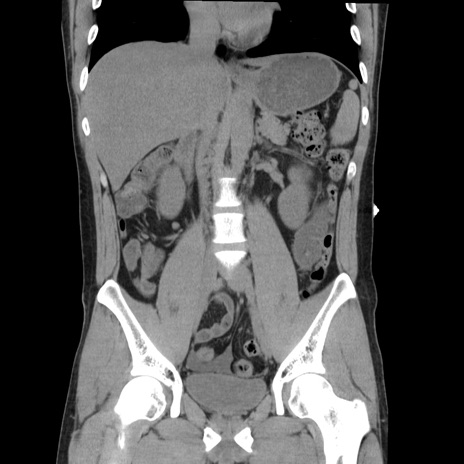

症例36(冠状断像)

【症例】20歳代 男性

【主訴】心窩部痛

【現病歴】今朝より上腹部痛あり。一旦軽快していたが再度出現したため救急要請。昨日夕に白身の魚を含む刺身を食べた。

【身体所見】BP 136/89mmHg、HR 74/min、BT 37.0℃、腹部:膨満、軟、心窩部に圧痛あり。反跳痛なし、筋性防御なし、腸雑音やや亢進あり。

【データ】WBC 17700、CRP 0.48